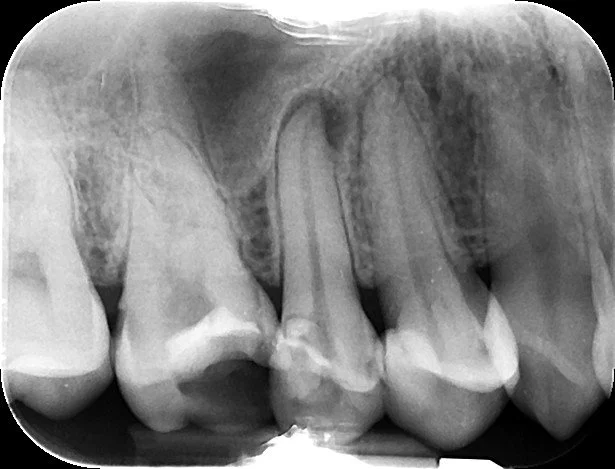

Endodontics